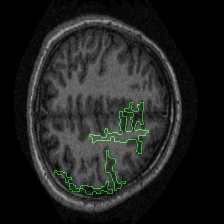

Figure 1 presents attribution maps generated using PWIG for a selection of MRI scans across all four diagnostic categories. The highlighted regions (in green) correspond to the areas that contributed most significantly to the model’s decision. Notably, we observe consistent emphasis on anatomical structures that align with clinical markers of dementia, including cortical and subcortical regions. For instance, in the moderate and mild dementia examples, the model focuses on regions exhibiting visible atrophy or abnormal morphology. In contrast, attribution maps for non-demented subjects appear more diffuse and less concentrated, reflecting the model’s detection of normal anatomical patterns.

The results in Figure 1 demonstrate that PWIG can effectively produce interpretable and clinically meaningful explanations for model predictions in medical imaging tasks.

Figure 1: PWIG attribution maps across dementia categories using the OASIS-1 dataset. Green overlays indicate regions with the highest attribution scores.